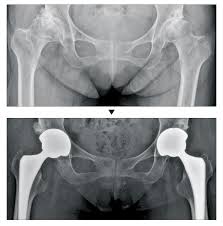

- 고관절 전치환술(Total Hip Arthroplasty, THA): 골관절염이나 류마티스 관절염, 골절 등에 널리 사용되는 방식으로, 관절 전체를 인공 관절로 교체합니다.

- 반치환술(Hemiarthroplasty): 대퇴골 두부 골절 등 특정 상황에 고관절 반만 인공으로 바꿔주는 방식입니다.